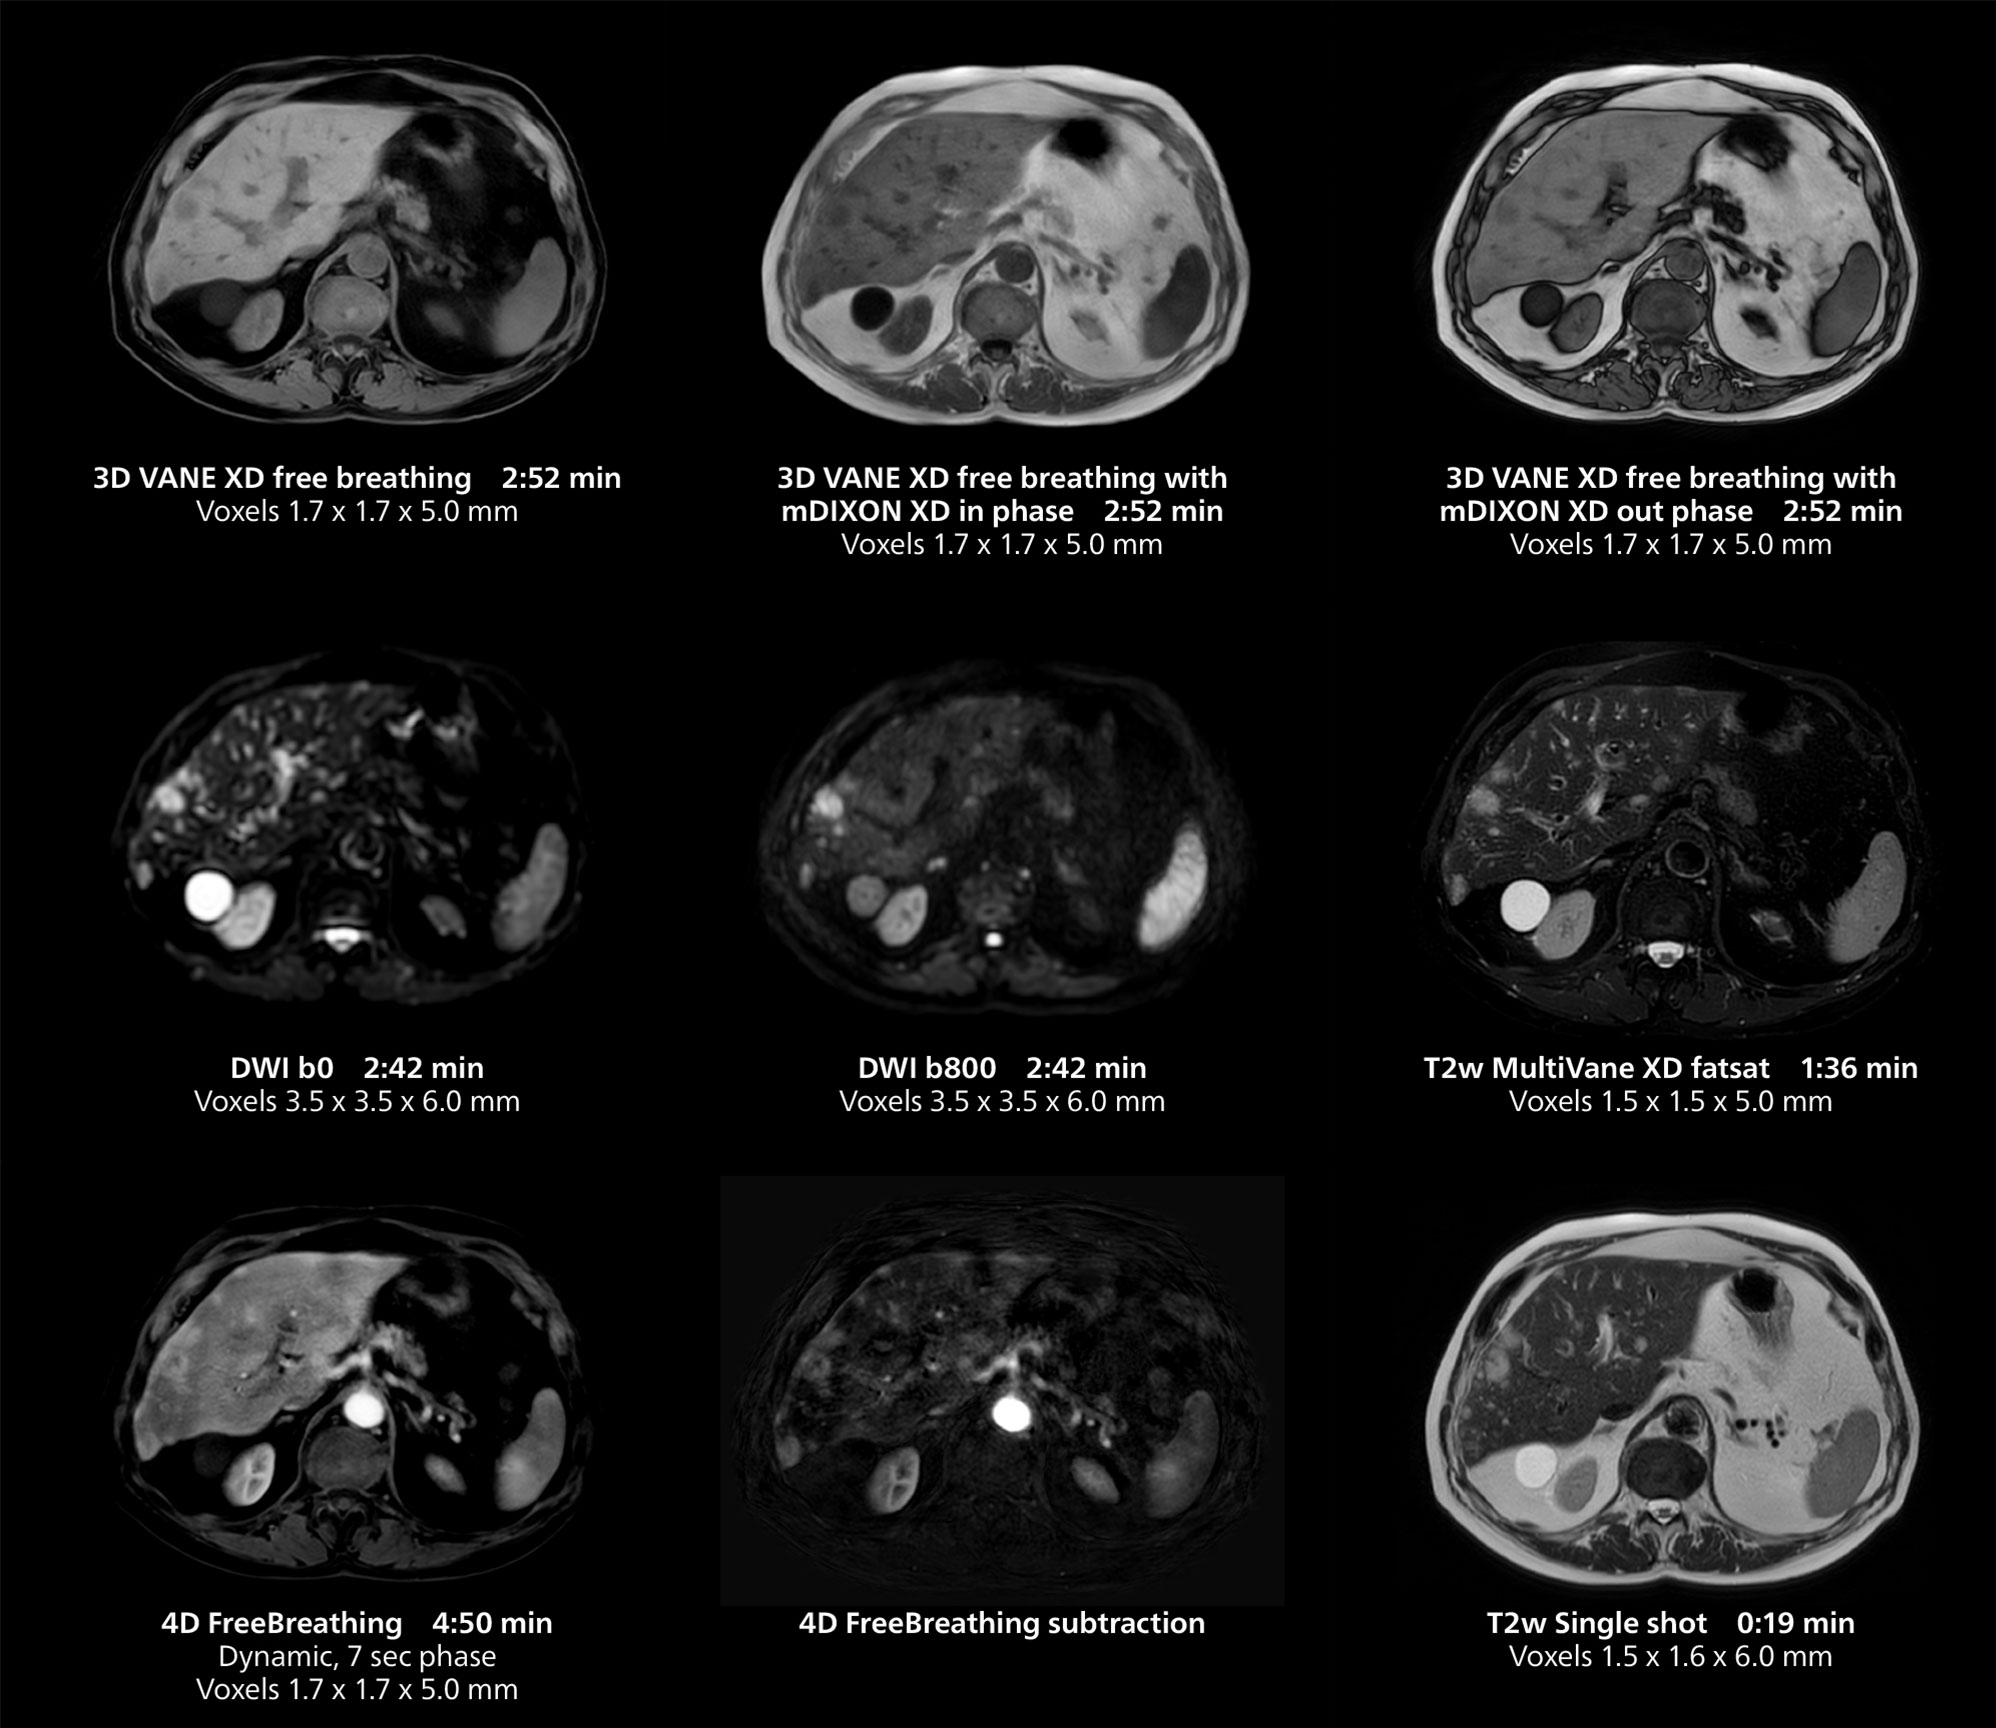

Dr. Gellée highlights the robust free-breathing scans as “the feature that makes the biggest difference in my daily work. The 3D free breathing sequences are very reproducible, and the axial acquisition is very good. For example, in endometriosis, which is one of my focus areas, it provides high contrast and good resolution so that I can see small details. We also use free breathing for liver and pancreas imaging. In multi-phase liver studies, 4D Free Breathing delivers 3-second temporal resolution, making a dynamic scan with more than one arterial phase possible.”

She also uses free breathing with 3D mDIXON to obtain in-phase, water and fat images in a single scan. “It is very reproducible before and after gadolinium, which makes it useful for liver imaging,” she adds.

This case includes 3D free breathing and 4D dynamic free breathing MRI of a metastasized liver. A high quality fatsat sequence with good resolution is obtained in 1:36 minutes with T2-weighted MultiVane XD.

This MRI case illustrates good resolution and imaging quality obtained within reasonable scan times using the MR 5300 1.5T system with the anterior torso cardiac coil that allows use of a large field of view (FOV).